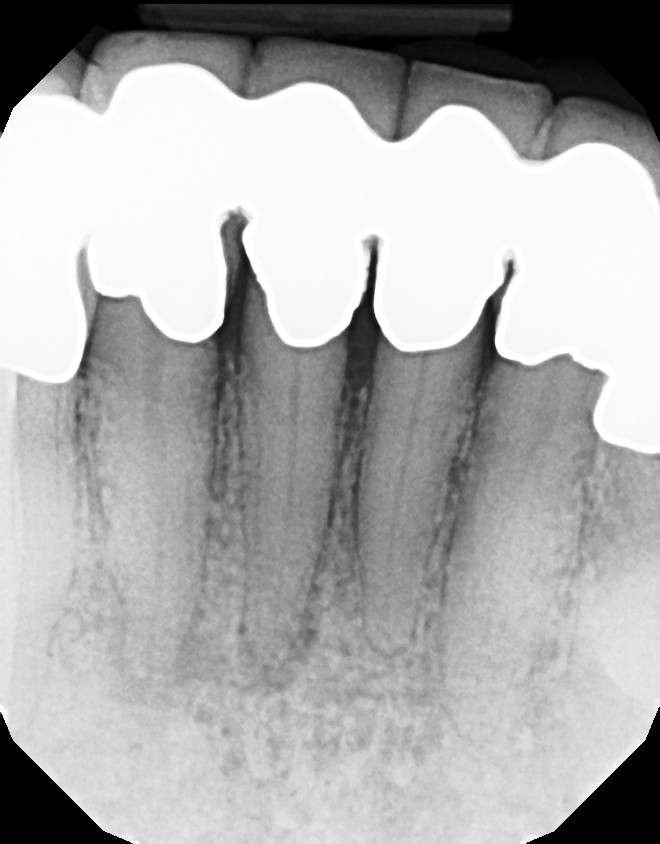

Long Island Endodontist shares his experience with root canal problems.

This is a multiple tooth / root issue that developed over time (4-5 years) under crowns where the nerves died and caused infection. After 3 months, bone regeneration (healing) occurred where infection was initially present. Endodontists (root canal specialists) are an important part of dental care for diagnosing and treating root issues.